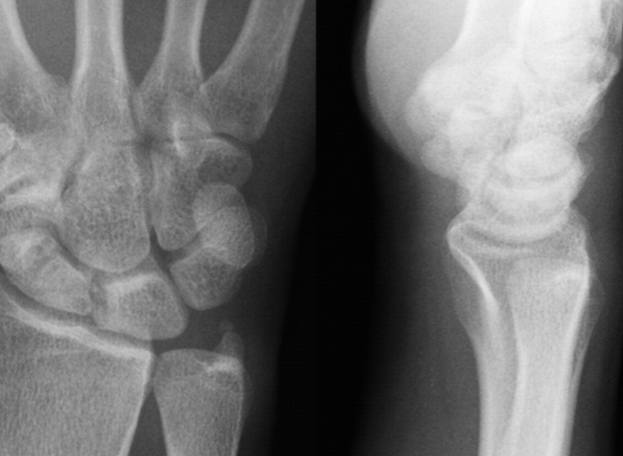

2. Bone management

It's not apparent, but it's bone health that's important. In general, men are no exception, although they often mention the dangers of women due to the rapidly weakening bone strength after menopause. This condition persists, resulting in osteoporosis and weakening of bones can cause various diseases. If osteoporosis occurs, you should consult a doctor first. However, it is recommended to maintain muscles and keep bones healthy through diet and exercise before osteoporosis occurs.